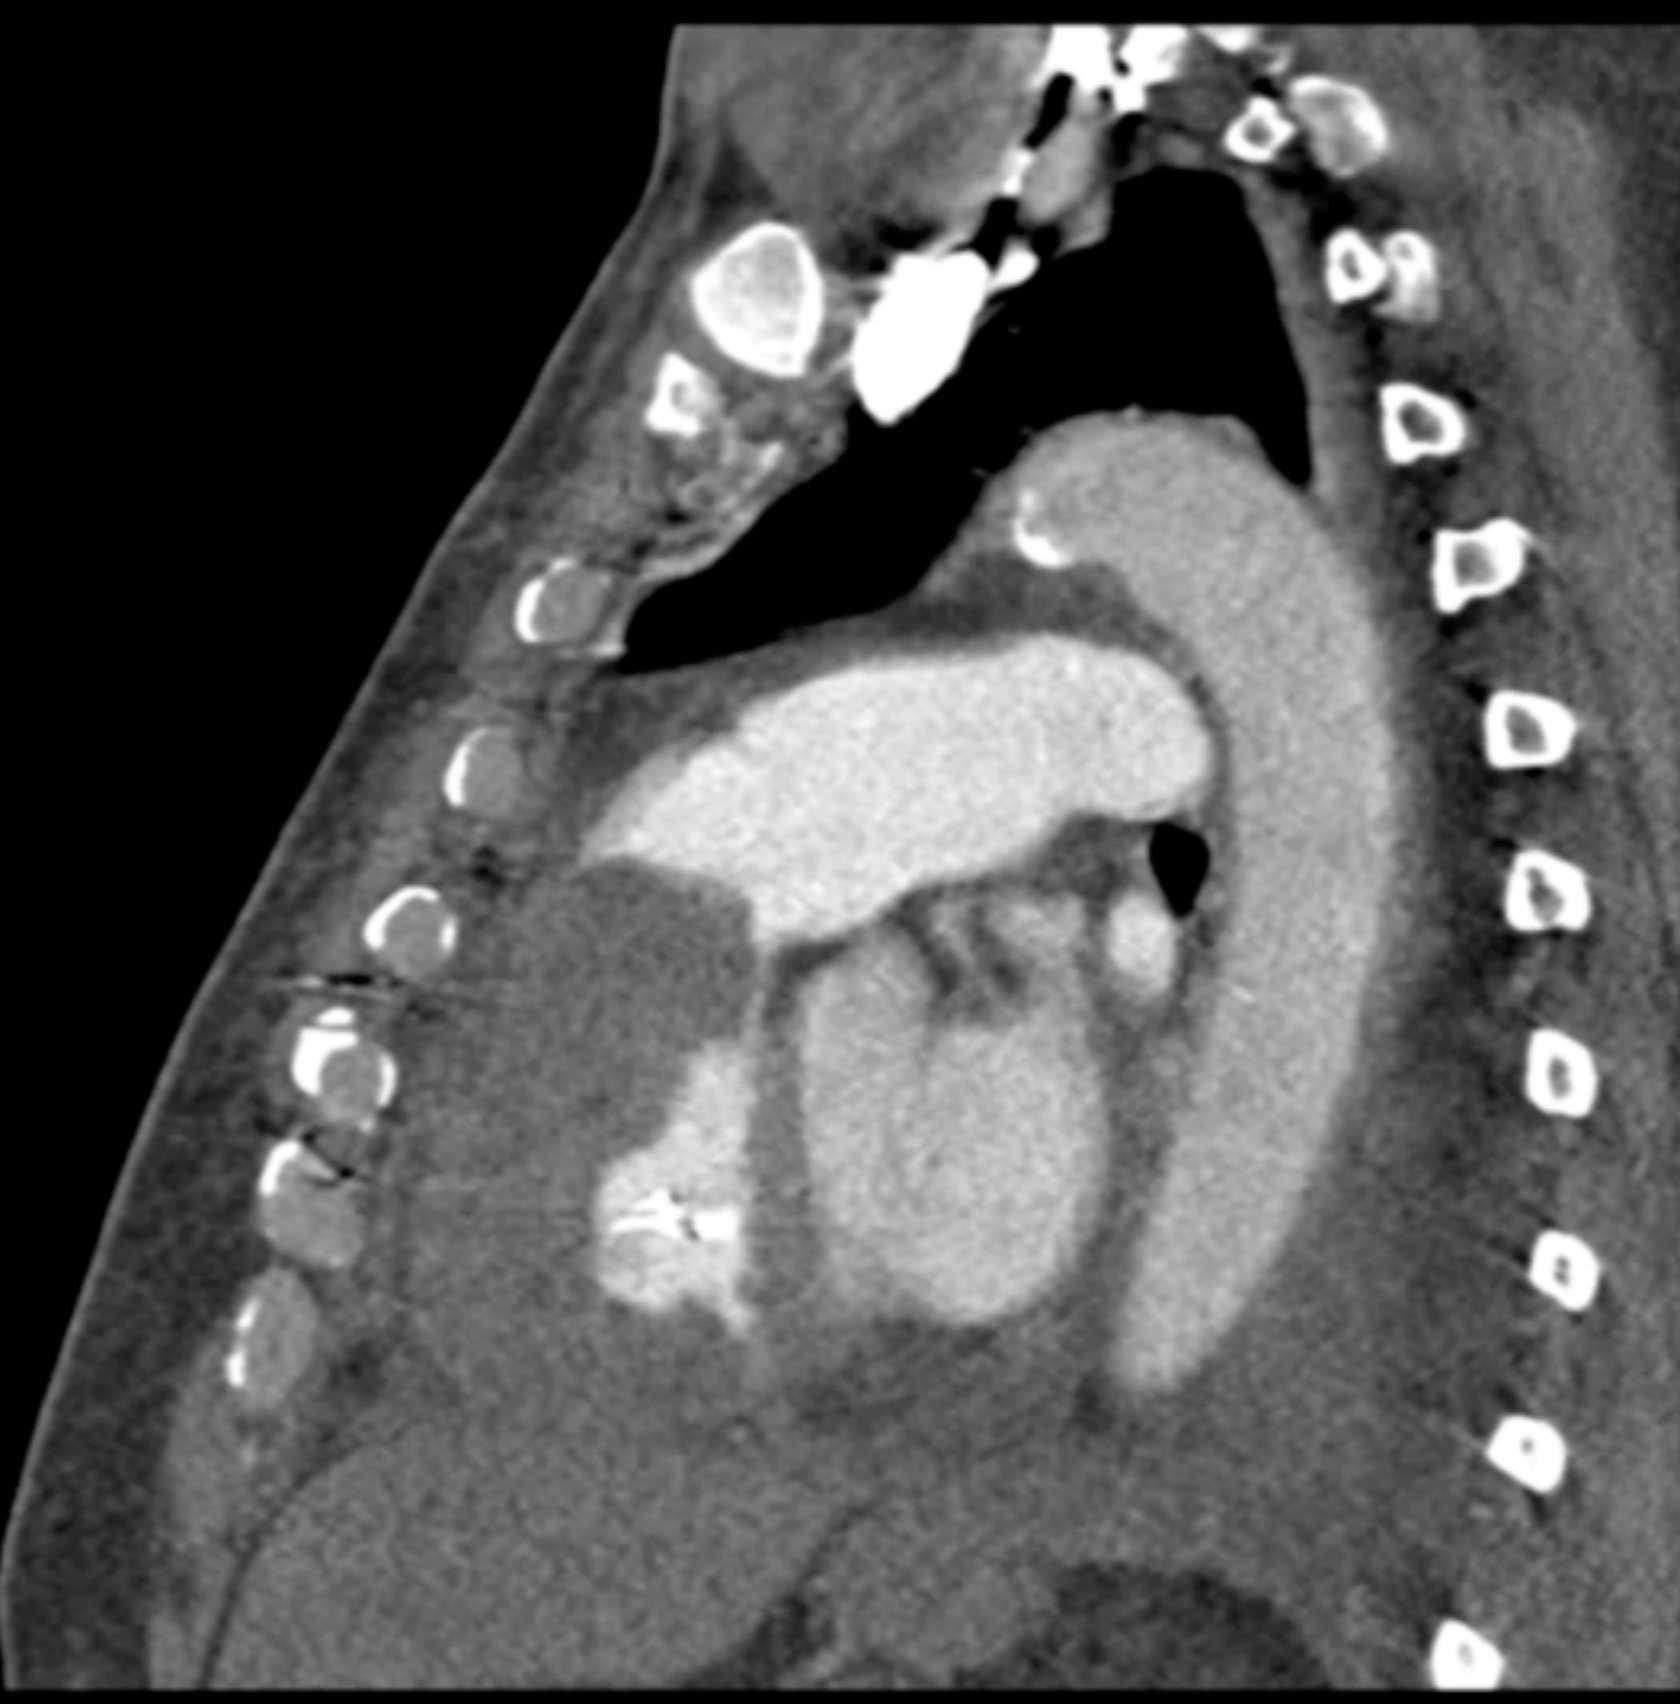

Primary Spindle Cell Carcinoma of the Right Ventricle